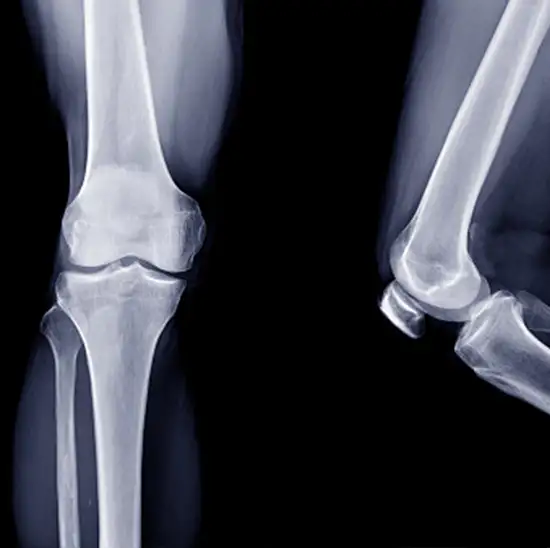

Knee X-rays are an imaging tool used to evaluate the knee joint's alignment, bone quality, and the number of degenerative changes. To obtain anterior-posterior (AP) and lateral (LAT) views, the X-ray beam is directed in front of the patient and then laterally.